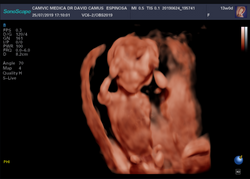

Ultrasonido 11-14 integral avanzado

Estudio 11/14 integral avanzado, también conocido como genético o de la nuca. Es un estudio que realizamos a los bebes cuando tiene entre 11 y 14 semanas, aproximadamente entre 2 meses y medio y 3 meses. En este estudio buscamos diversos marcadores ecográficos como la translucencia o grueso de la nuca, el hueso nasal, marcadores del corazón fetal, así como una revisión detallada de la anatomía del bebe en busca de malformaciones, ya sea en su cuerpo, órganos internos o en su cara, así como marcadores hemodinámicos.

Ejemplo de nuestro reporte